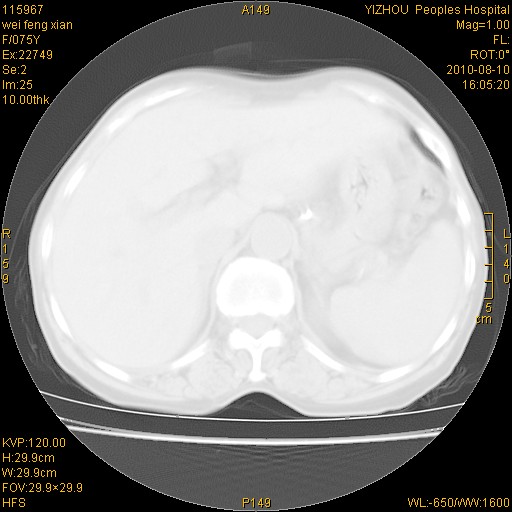

标题: CT28313:两肺弥漫性病变 [打印本页]

标题: CT28313:两肺弥漫性病变

女,75岁,患者反复头昏乏力面色苍白3年,再发10天入院。临床贫血查因。

双肺间质增生并右肺上叶炎性改变,不除外右肺上叶结核病肺内播散

考虑右肺上叶炎症合并双肺结核可能性大,建议上传纵隔窗ct图片。

双肺结核可能性大

考虑尘肺并结核;右上肺支气管扩张!

结核、尘肺、支气管肺泡癌都不能除外

右肺上叶继发性肺结核伴肺内血型播散!

考虑右肺上叶继发性肺结核伴两肺播散。